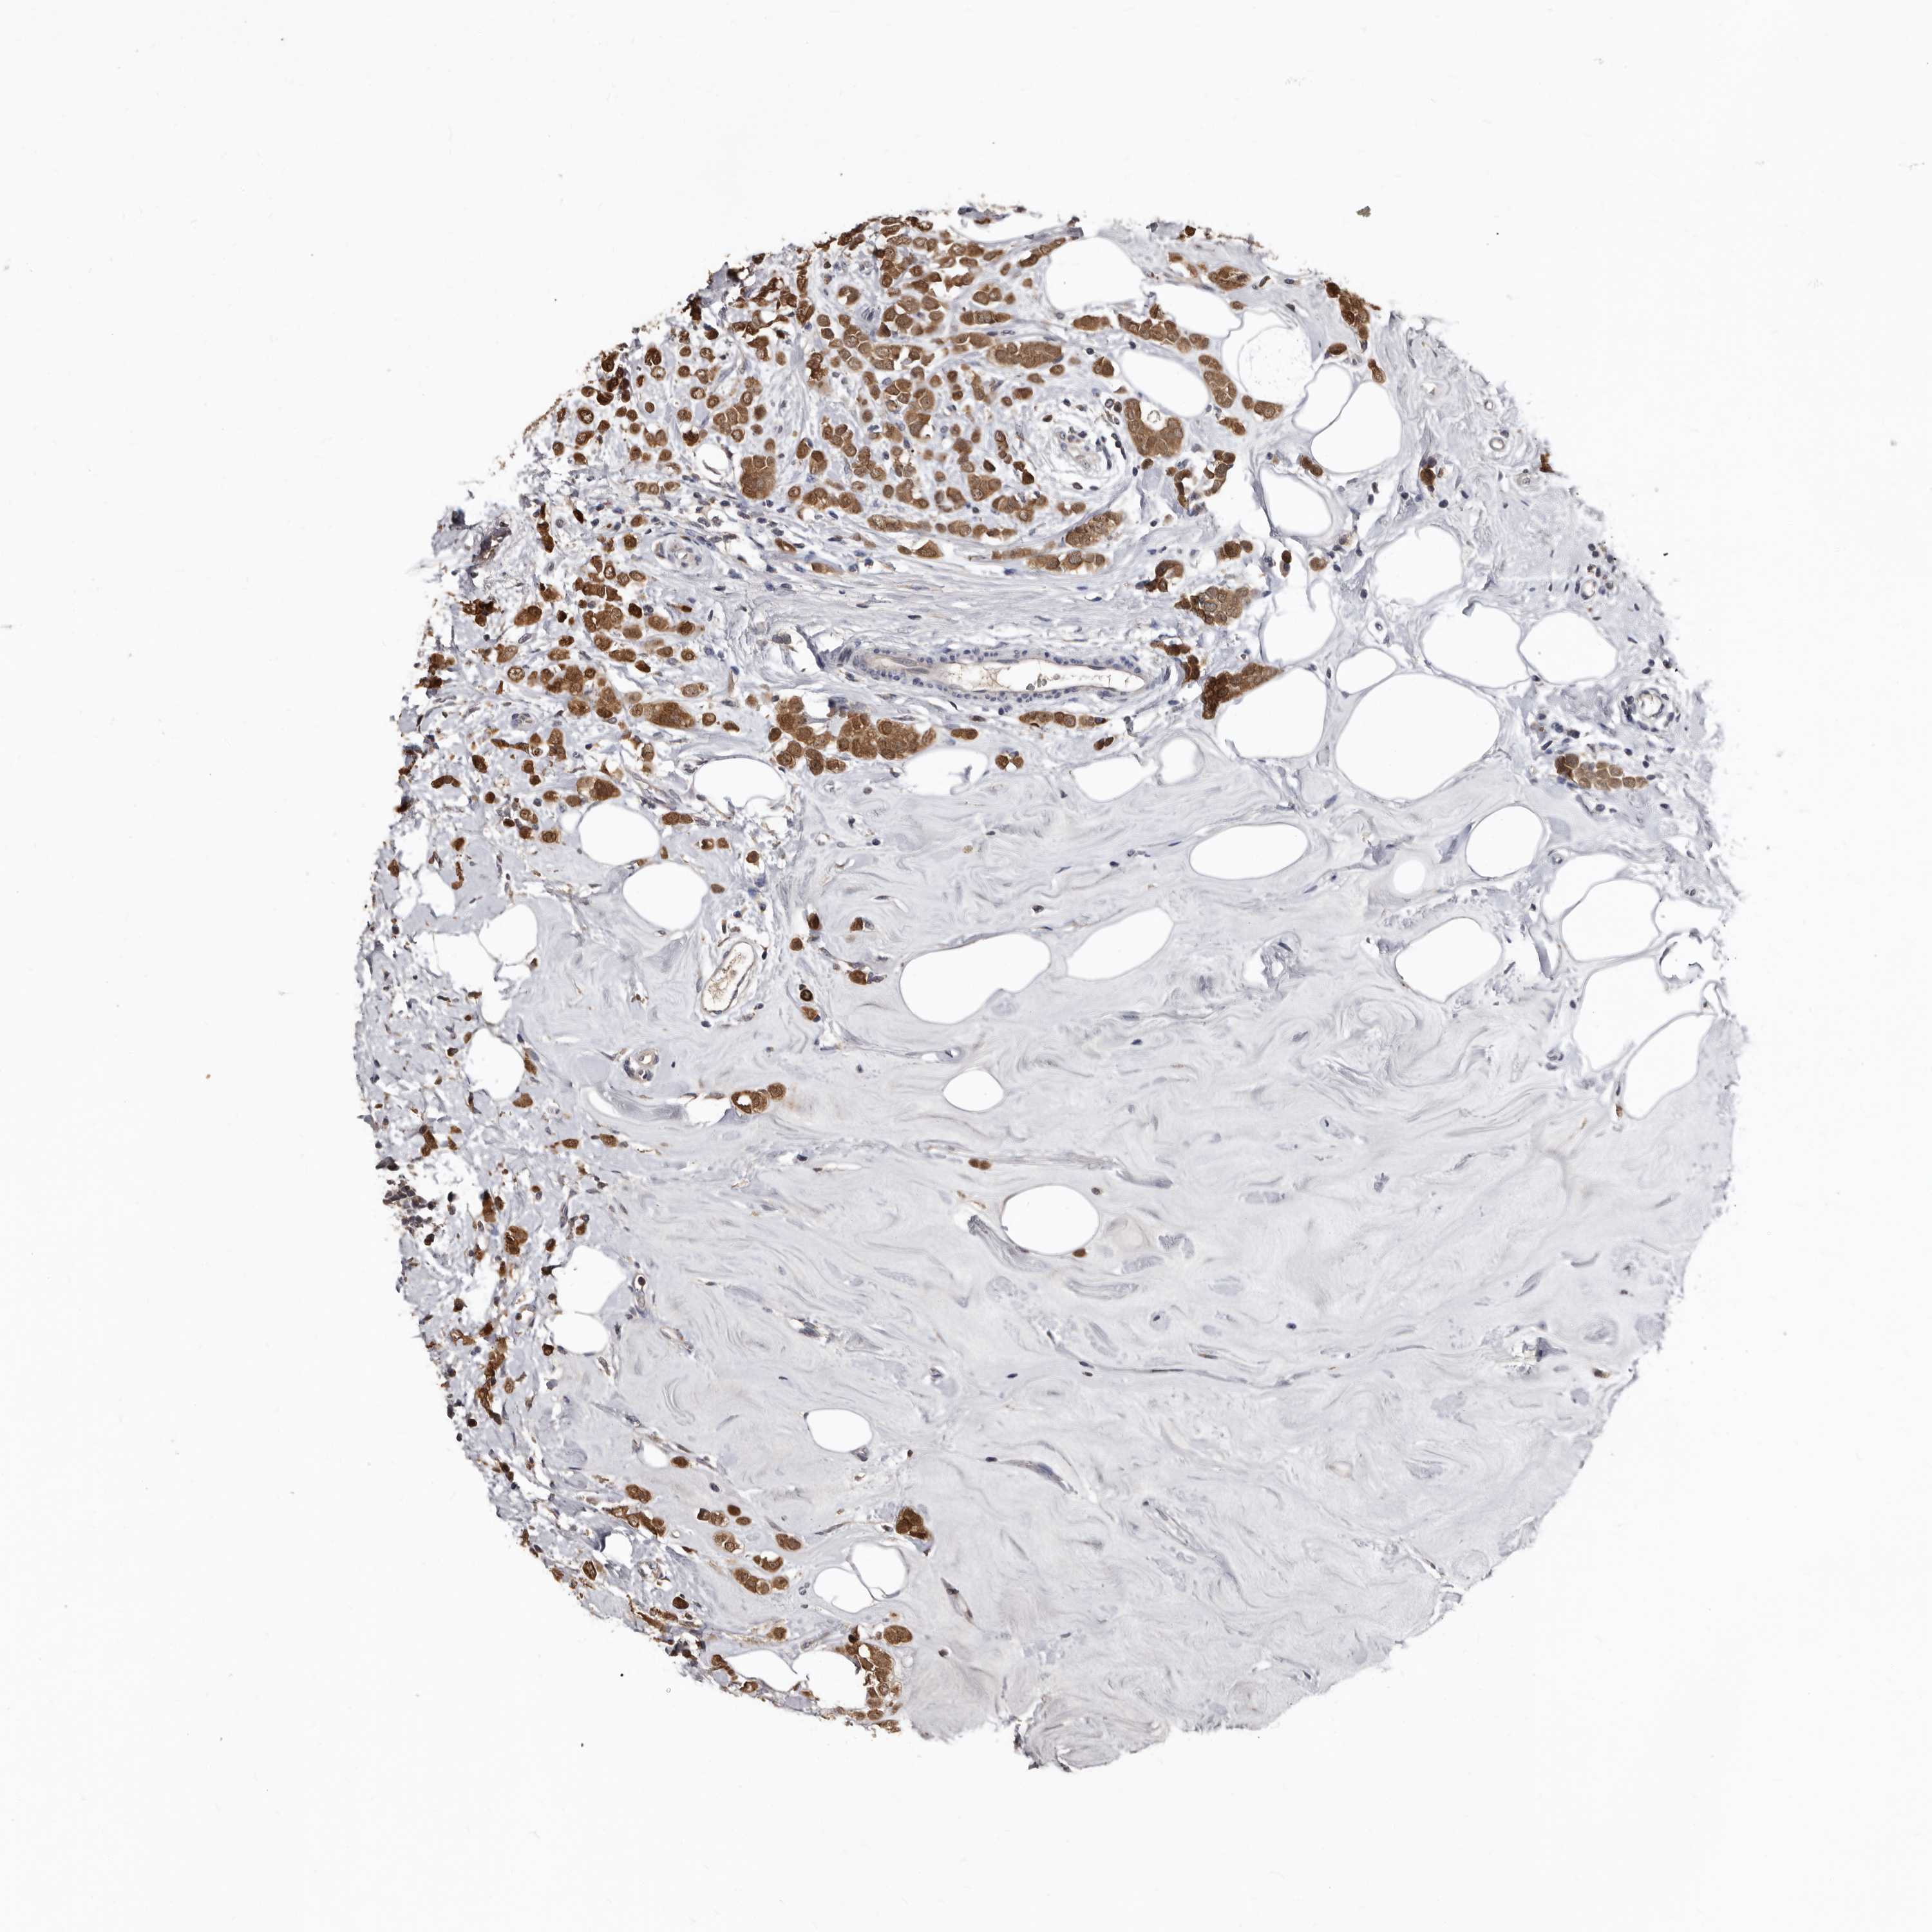

CANCER BREAST CANCER Show tissue menu

BRCA TCGA BRCA VALIDATION PROTEIN EXPRESSION

Breast cancer

Human cancer